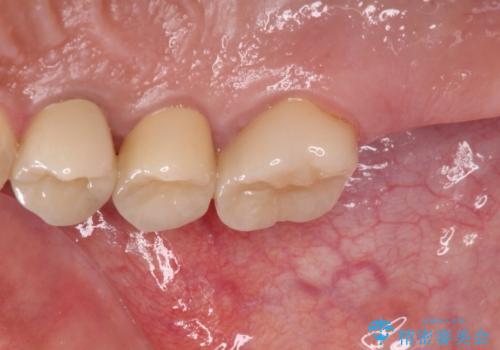

- 奥歯を治療しようと他院で開始したものの、放置してしまったとのことで来院された患者様です。

外れてしまった銀歯や穴の空いた仮歯などあり、適合の悪い被せものと合わせて、セラミッククラウンやセラミックインレーにて治療と行うこととしました。

億劫に感じて治療を先延ばししていたそうですが、始めてみるとスムーズに治療が終わり、早く始めておけば良かったと仰っていました。